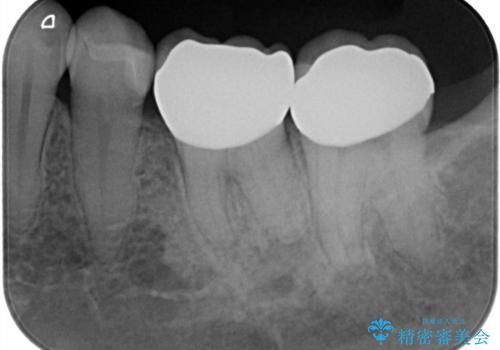

- ご友人との会話中などに、下の歯に入れてあるメタルインレーが見えてしまうのが気になり、やり変えを希望された患者様です。審美性、清掃性に優れたセラミックでの治療を希望されたため、セラミックインレー、クラウンで治療いたしました。

口を開けた際の見た目が向上し、非常に満足いただけました